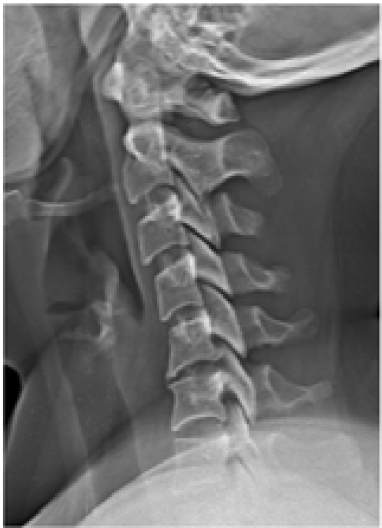

Evaluation and Management of Cervical Radiculopathy from Disc Herniation and Degenerative Disorders

Selvaraj Periyasamy, Prem James Charles and Ashwin Narasimhaprasad. 13(12): 18-27.